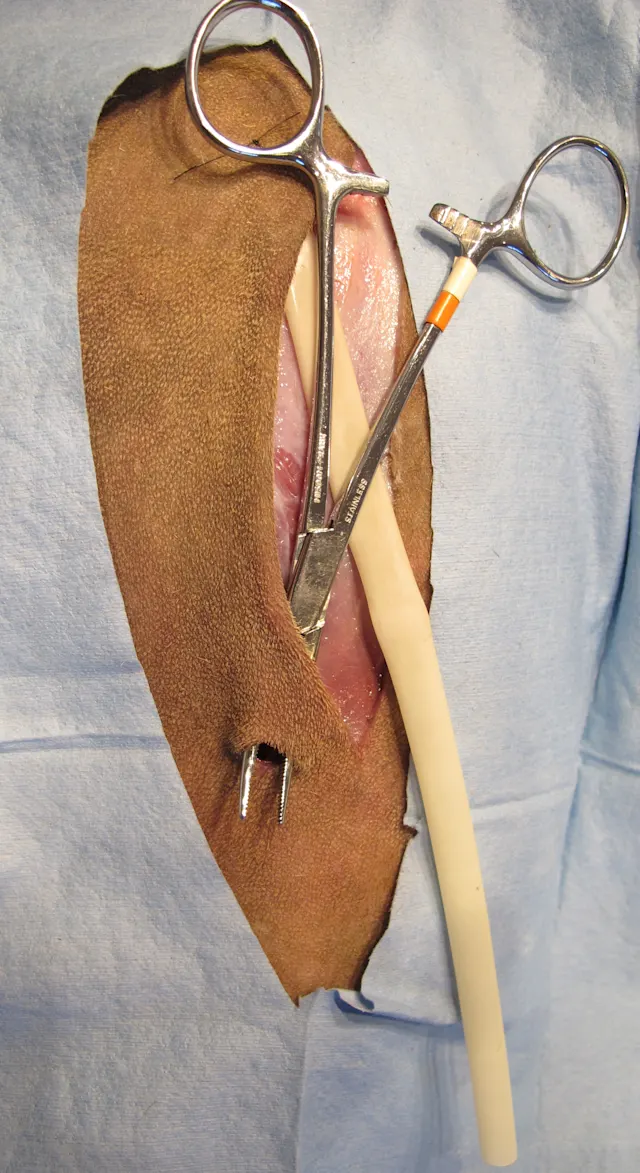

Secure the drain to the skin. (A) An interrupted suture through one side of the skin incision and the drain works well for passive drains. (B) Secure active drains with a Chinese finger trap suture or similar friction suture.

A